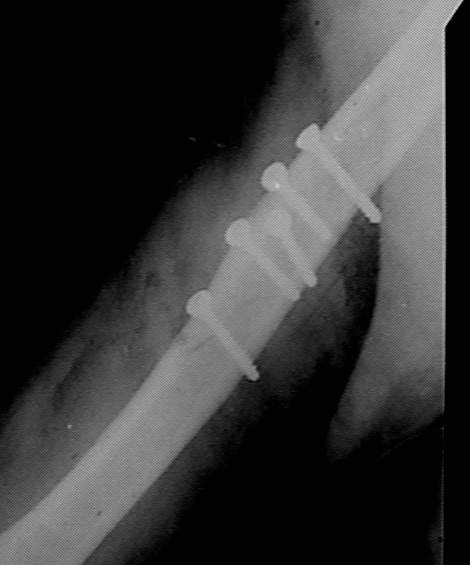

Больная 45 лет оперирована в июле 2002 г, иммобилизация в течение 3 месяцев. После операции были явления неврита лучевого нерва, которые в последующем исчезли. Во время проведения ЛФК отмечается появление болей, патологическая подвижность в месте перелома, деформация плеча.

Проводилась консультация на форуме октябрь 2002, по дальнейшей тактике лечения . Из-за поломки дрелей пришлось ограничиться закрытой репозицией и иммобилизацией торакобрахиальной повязкой в течении 3 мес. Проводили стимуляцию сращения препаратами:"Миокальцикс" и "Ca D3 Никомед" Рентгенконтроль 14.01.03 . Клинически сращение хорошее.Интересно узнать какие препараты используются вами для стимуляции сращения?

На мой взгляд, в данном случае, перелом сросся скорее не благодаря, а вопреки "лечению".

Считаю неграмотным вкручивание винтов с конусными или закругленными головками, так как они вклиниваясь в кость, раскалывают ее. Два крайних винта на представленных снимках захватили только по одному из отломков. О

серкляже и говорить не хочется: циркулярно жгутирует кость, зачастую удаление проволоки травматичнее ее установки и т.д. За двадцать лет работы ни разу не наладывал торакобрахиальную гипсовую повязку т.к. считаю ее издевательством над пациентом. При таких грубых нарушениях современных принципов травматологии странно слушать вопросы о препаратах, стимулирующих сращение. За деньги, которые потрачены на приобретение таких дорогих препаратов как миакальцик, Са Д3, остеогенон, Вы могли бы приобрести нормальные металлоконструкции для полноценного остеосинтеза и запасную дрель.

Re: Перелом плеча

Андрей 15 Март 2003, 02:44

Подобные переломы прекрасно срастаются без операции.

Операция в данном случае может быть оправдана только ранней реабилитацией, которая возможна только при стабильном остеосинтезе: в конкретном случае -длинная пластинкка.

Метод остеосинтеза в данном случае выбран не удачно изначально.